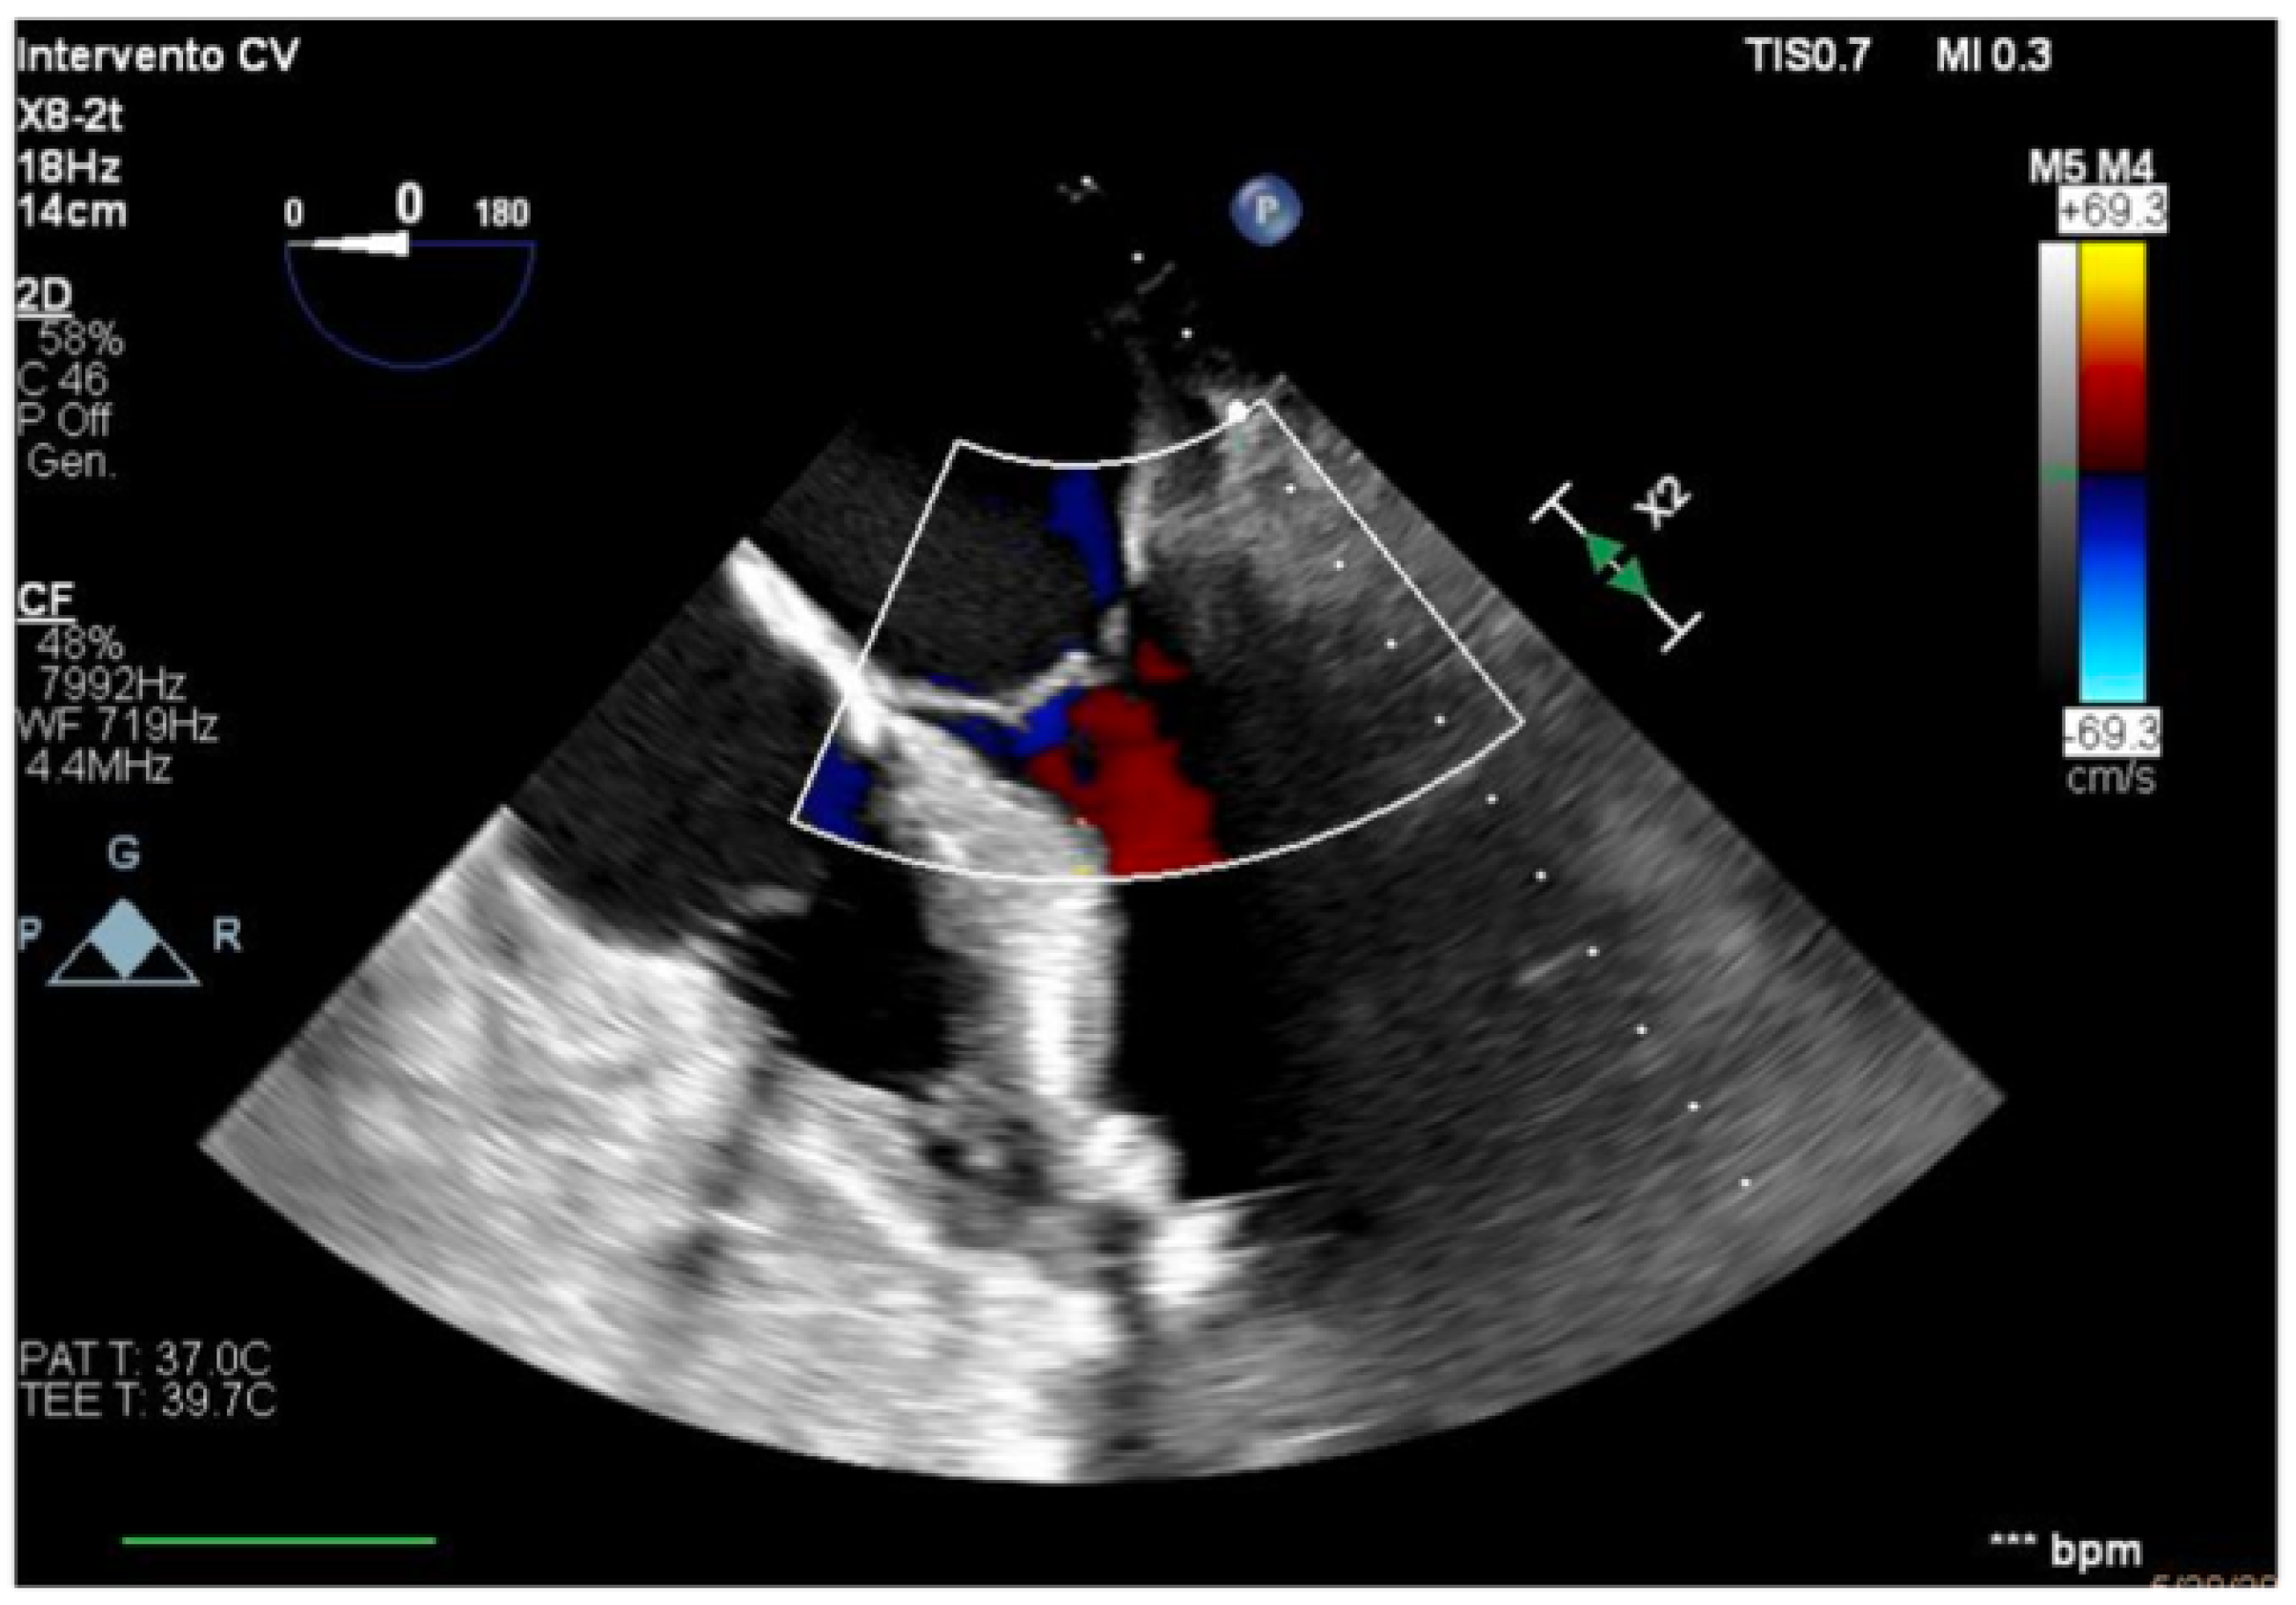

We describe a case of a 75-year-old woman affected by a post-myocardial-infarction ventricular septal defect (VSD) and a left-ventricle (LV) apical aneurysm. The patient underwent surgery for VSD closure and aneurysm exclusion. The patient had a STEMI (ST-elevation myocardial infarction), with evidence of occlusion of the anterior interventricular artery, for which thrombus aspiration and stenting of the left coronary artery and proximal anterior interventricular artery was performed. Then, she developed cardiogenic shock with pulmonary edema and thus required the support of an IABP (intra-aortic balloon pump) of C-PAP and levosimendan in continuous infusion for 24 h. Seven days after the event, a large post-infarct VSD at the apical level with a left–right shunt occurred. She was therefore transported from the spoke center to our hospital and underwent surgical treatment, namely, post-infarct VSD closure and exclusion of a left ventricular aneurysm. The intra-operative transesophageal echocardiography showed concentric LV remodeling, slight dilatation, LVEF 28% (Figure 1), and akinesia of the mid-apical segments in toto with aneurysmal evolution (Figure 2).

Figure 1. Mid-esophageal four-chamber view.